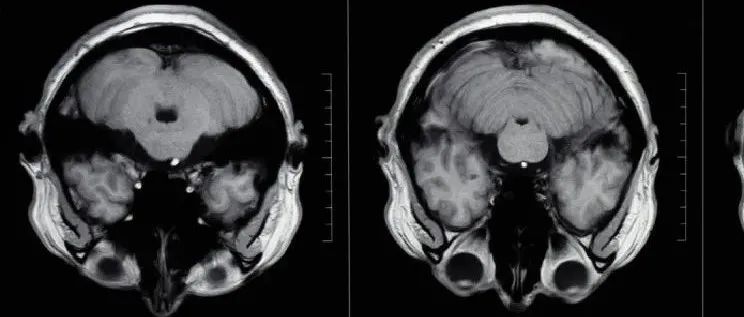

最硬核的戒烟广告——吸烟30年,肺长这样!| 世界无烟日

医脉通编辑整理,未经授权请勿转载。引言:吸烟可能缘于一次偶然,但戒烟应是一种必然!了解烟草的危害,科学戒烟,为了自身更是为了下一代的健康。1987年11月,世界卫生组织建议把每年的4月7日定为世界无烟日。自1989年,世界无烟日改为每年的5月31日,因为第二天是国际儿童节,希望下一代免受烟草危害。今年,我们迎来了第35个世界无烟日。 我国烟民超过3亿,7亿人遭受二手烟危害,每年百万人因此死亡!...